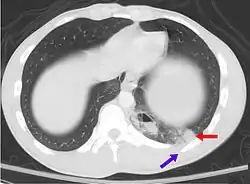

Pulmonary contusion due to trauma is an example of a condition that can be asymptomatic with half of people showing no signs at the initial presentation. The CT scan shows a pulmonary contusion (red arrow) accompanied by a rib fracture (purple arrow).